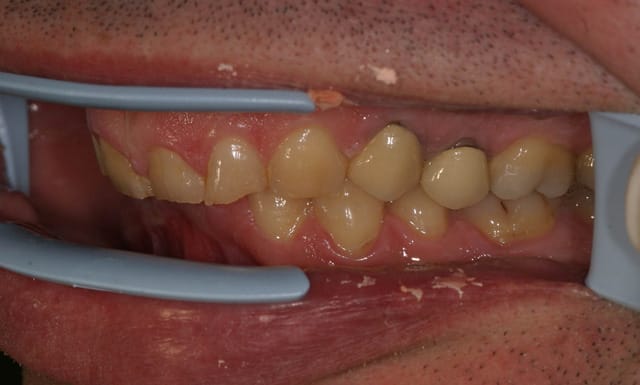

ce patient, 40 ans, non fumeur, sans de pb de santé particulier consulte pour un problème esthétique sur la 53. il est aussi inquiété par l'usure de ses incisives.

l'abrasion des incisives, l'éggression des groupes incisivo-canin maxillaire et mandibulaire pour compenser cette abrasion, et l'occlusion me laissent dubitatif.

Regarde les niveaux gingivaux, ça devrai te mettre sur une piste.......

Si tu harmonises la ligne des collets chirurgicalement, tu récupères une hauteur

coronaire compatible avec la prothèse.

Sur les modèles seul les incisives et canines sont abrasées. Les molaires et PM ne montrent aucunes facettes d'usure.